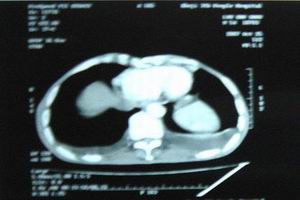

3.甲状旁腺功能减退症因脑组织钙化可出现锥体外系症状,如不自主运动、手足徐动、扭转痉挛、震颤、小脑共济失调、步态不稳等,易被误诊为神经系统病变。应仔细观察有无低钙血症及其相应的临床表现,同时采用X线或CT检查脑组织钙化病变,将有利于甲状旁腺功能减退症的诊断。

2.影像学检查头颅X线摄片约有20%显示基底节钙化,少数病人尚有松果体及脉络丛钙化;CT扫描较之X线摄片更敏感,能更早及更多地发现颅内钙化灶。 医学百科网 | YxBaike.Com

2.癫痫样发作及其他神经症状表现除了观察低钙血症及其临床表现外,用X线或CT检查脑组织钙化病变,对诊断很有帮助。